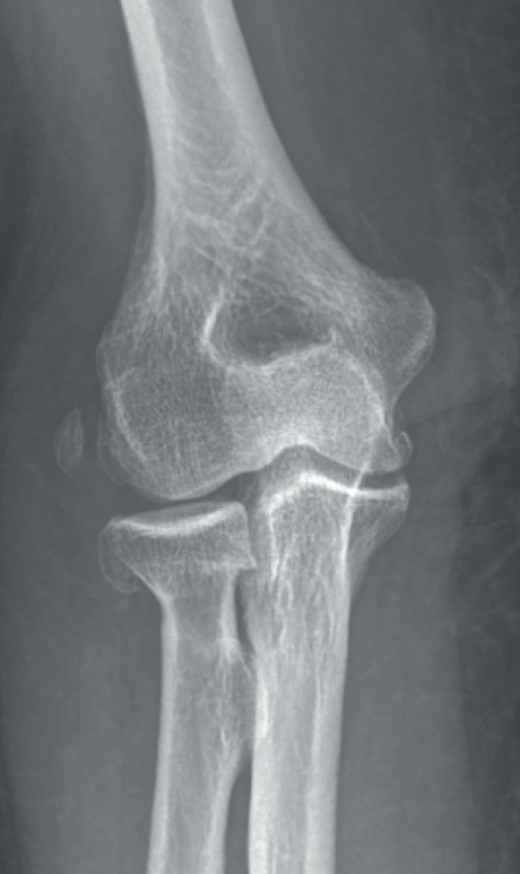

- Radiografía simple: puede orientarnos hacia una inestabilidad si se objetivan signos indirectos, tales como calcificaciones en la inserción ligamentosa, que sugieran antecedente de avulsión ligamentosa (Figura 7).

Signos de haber tenido fracturas en la cabeza del radio o la coronoides, aunque ya estén consolidadas, nos ponen en el contexto de un posible antecedente de luxación acompañando a las fracturas. También la presencia de fractura con fragmento cortical posterolateral del húmero, que ha sido considerado como el “Hill-Sachs del codo”(12)(Figura 8).

Y, por supuesto, signos directos, si objetivamos la articulación claramente subluxada (Figura 9).